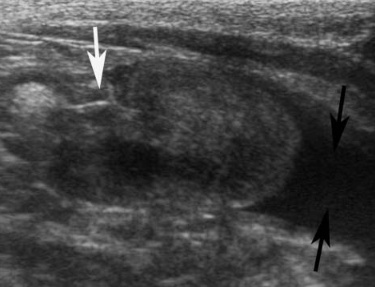

저에코성 혹은 무에코의 수질(medulla)을 확장된 신우로 혼동하지 않는 것이 중요합니다. 신우 확장은 보통 초음파 횡단면(transverse plane)에서 더 쉽게 보입니다. 신우 안의 액체는 심장 모양 또는 초승달 모양의 무에코성 부위로 보이며, 신장 능선(renal crest)을 감싸는 형태를 보입니다(그림 1).

신장을 배 측면(dorsal plane)으로 보면 신우 확장은 선형~타원형으로 보입니다. 확장이 점점 심해지면 신우는 둥근 모양을 나타냅니다(그림 2).